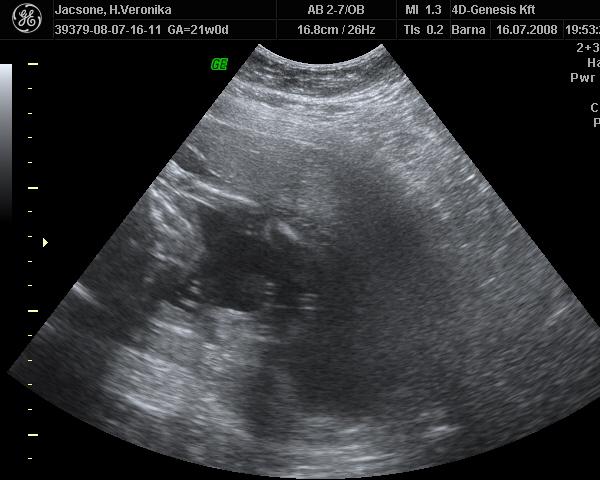

Rólunk:hétfőn voltam uh-n,minden rendben volt,a nemét nem tudta megmondani a doki,mert azt mondta szar a gép,nem tudja kivenni. :roll: :? :twisted:

Aztán szerdán voltam az Istenhegyin genetikai uh-n.A babó teljesen elbújt a méhlepény mögé és semmi nem látszódott belőle! :shock: Ráadásul meg sem mozdult,25 percnyi "lökdösés" után is csak intett egyet.A doki aggódott hogy miért nem mozog,teljesen a frászt hozta rám.Egyébként rendszeresen érzem hogy mozog,úgyhogy remélem csak éppen bealudt. :oops: